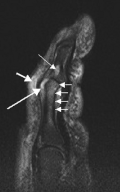

T2-weighted MRI (sagittal) of index finger in PsA (mutilans form) showing probable erosion (increased signal) at base of the middle phalanx (long thin arrow), synovitis at the proximal interphalangeal joint (long thick arrow), soft tissue edema (short thick arrow), and diffuse bone edema (short thin arrows) of the proximal phalanx. -

(a) STIR Sagittal MRI of ankle showing enthesitis at Achilles tendon insertion (thick arrow), synovitis of ankle joint (long thin arrow), and bone marrow edema at tendon insertion (short thin arrow). T1-weighted images, before (b) and after (c) contrast, show enthesitis (large arrow) and bone erosion at tendon insertion (short thin arrows).